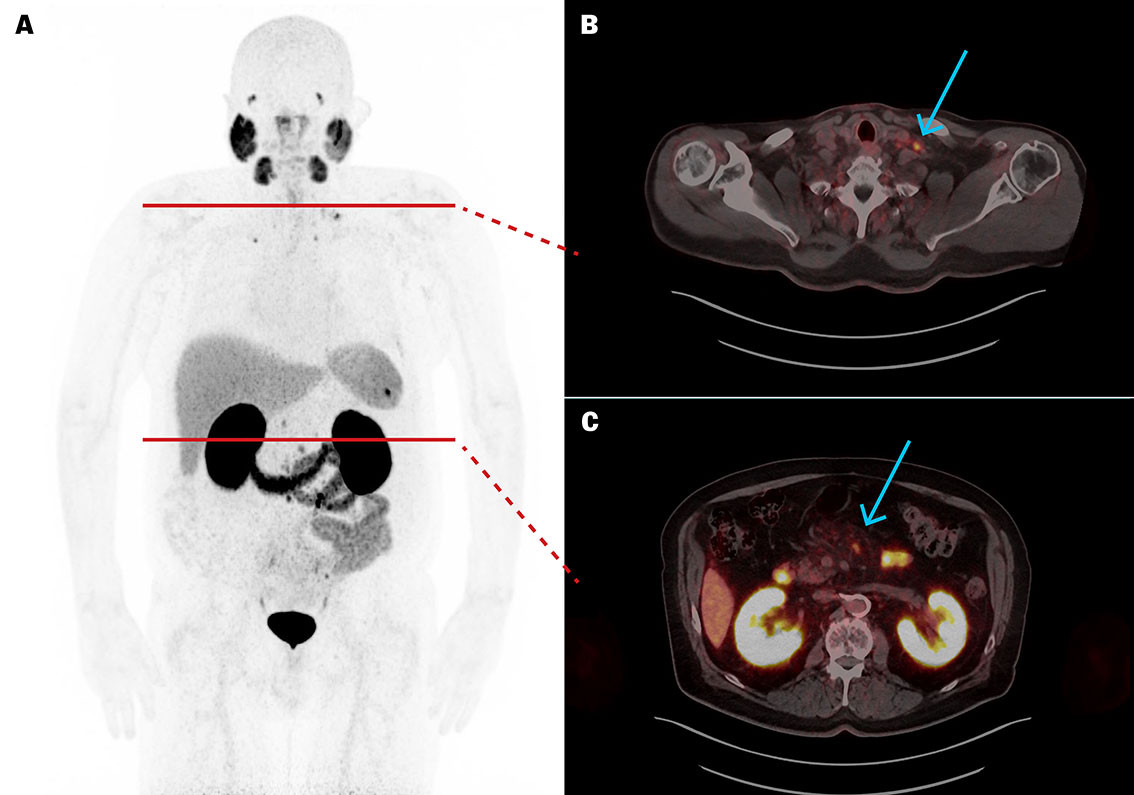

Fem uker etter femte behandling var p-PSA 1,8 µg/L. [⁶⁸Ga]PSMA-11 PET/CT viste betydelig størrelsesreduksjon av metastasene (figur 2), der den største (mållesjon) hadde redusert diameter fra 10 til 4 mm. Ut over nedsatt matlyst og forstoppelse ble behandlingen godt tolerert uten affeksjon av nyre-, spyttkjertel- eller benmargsfunksjon.